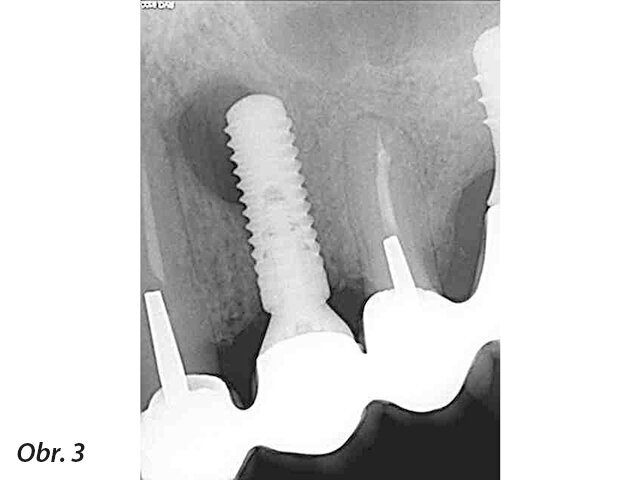

Obecně termín „periapikální léze u implantátu“ (PIL – periapical implant lesion) popisuje radiografický nález kolem apexu implantátu, bez vztahu k dalším periimplantátovým tkáním nebo sousedním zubům. Klinické vyšetření potíží pacienta nemusí vždy indikovat patologický nález, a pokud ano, tak se definice tohoto pojmu překrývá s „retrográdní periimplantitis“ (RPI – retrograde peri-implantitis). RPI má podobnou definici, ale je doprovázeno stížnostmi pacienta a často i klinickými nálezy (obr. 1–3).

RPI manifestuje skrze radiografické a také rozmanité klinické nálezy. V případě RPI je zde přítomna retrográdní infiltrace patologických mikroorganismů, které osídlí apex implantátu. Tato infiltrace často pochází od sousedního zubu, není to ovšem jediná příčina RPI. Další příčiny mají vztah k operačnímu protokolu, protetice a plánování implantace. Ve většině případů vede k diagnóze kombinace více než jednoho faktoru. Laterální defekty, mobilita implantátu a pooperační zánět vztahující se ke zbytku fixtury implantátu nebo zánět periimplantátových tkání jsou z této definice vyloučeny.

Jak PIL, tak RPI se často objeví jako náhodný radiografický nález až léta po zavedení implantátu a protetické rehabilitaci. Pokud jsou doprovázeny klinickými nálezy jako je pozitivní poklep, stížnosti na skus nebo syndrom bolesti, rozlišujeme dvě doby: a) po šesti týdnech od zavedení a b) čtyři až osm týdnů po zatížení. Stížnosti na bolest za delší dobu od zatížení jsou ve většině případů indikací křížové kontaminace od sousedních zubů.